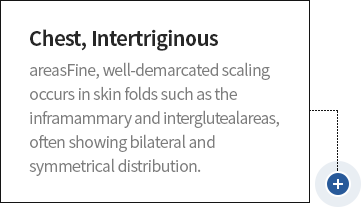

Scalp inflammation can cause significant hair loss.

Avoid alcohol and overexertion to manage the condition,

and seek proper treatment when early symptoms like dandruff or itching appear.

It's important to reduce physical fatigue and mental stress.

Psychological stress and overwork can worsen the condition,

so it’s important to stay calm and relaxed.